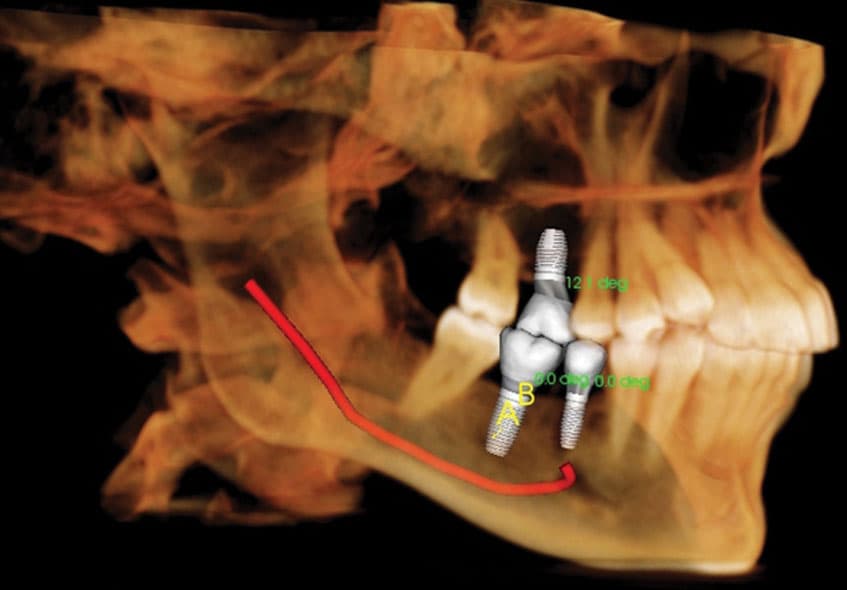

A dental CT scan is a type of X-ray that produces 3D images of the teeth, jaws, and surrounding structures. This technology is particularly useful in surgical planning for dental implants, as it can provide detailed information on bone quality and nerve canals. Unlike traditional X-rays, which only show a flat image of the teeth and jawbone, a CT scan provides a more detailed and accurate picture of the area.

Dental CT scans are necessary for a variety of reasons. For example, they can help diagnose and treat conditions such as impacted teeth, cysts or tumors, bone defects, or nerve canal involvement that could affect treatment. They are also useful in planning for dental implants, root canals, wisdom teeth extractions, and orthodontic treatments such as braces or Invisalign.